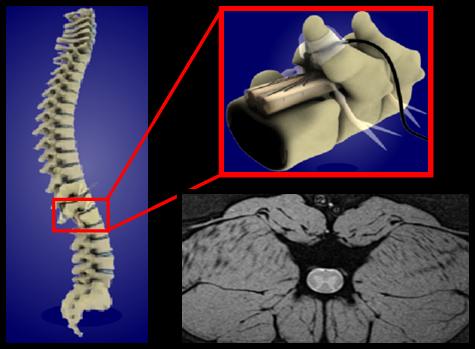

Spinal Cord Injury

Areas of research:Spinal Cord Injury